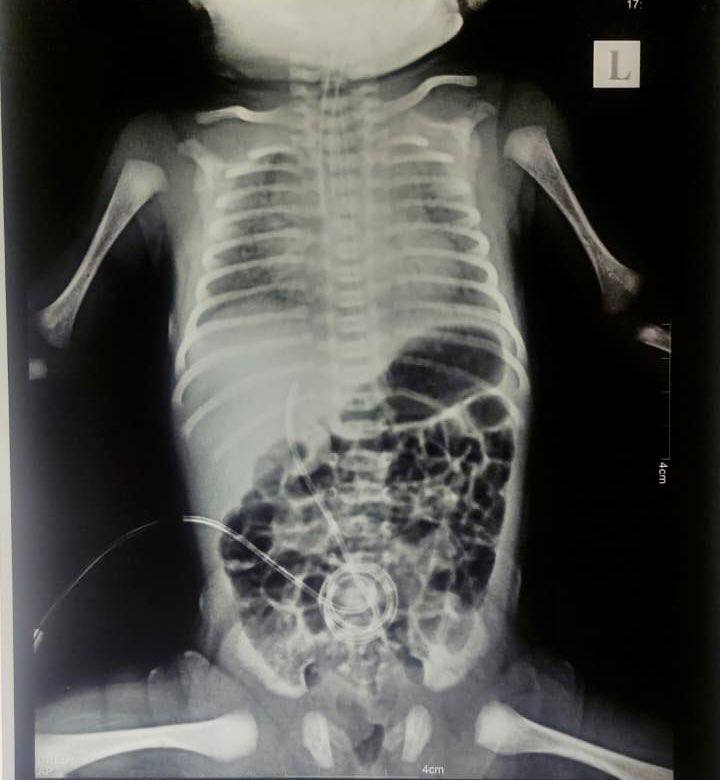

"WHITE LUNG SYNDROME" IS A COVID19 "VACCINE" ADVERSE REACTION:

"Fully Vaccinated Mother’s Dying Newborn With White Lungs. A pattern of Multisystem Inflammatory Syndrome in Neonates"

“We have a dying infant with MIS-N, born to a vaccinated mother who never had any symptoms of Covid, and no positive test, and yet the doctors are blaming Covid!”

Newborn diagnosed with Multisystem Inflammatory Syndrome in Neonates, MIS-N

The paediatrician states that this is a pattern he is seeing in his practice and has lost 4 out of 5 babies born with this condition.

He states that the common pattern is;

•No signs of Covid infection in vaccinated mothers

•High “anti-Spike” (S1) antibody counts in babies

•Uneventful pregnancy, up to the point when the baby is born, revealing dysfunctional lungs, infant unable to breathe on their own, and the newborn ends up being hooked up to the highest throughput ventilator."